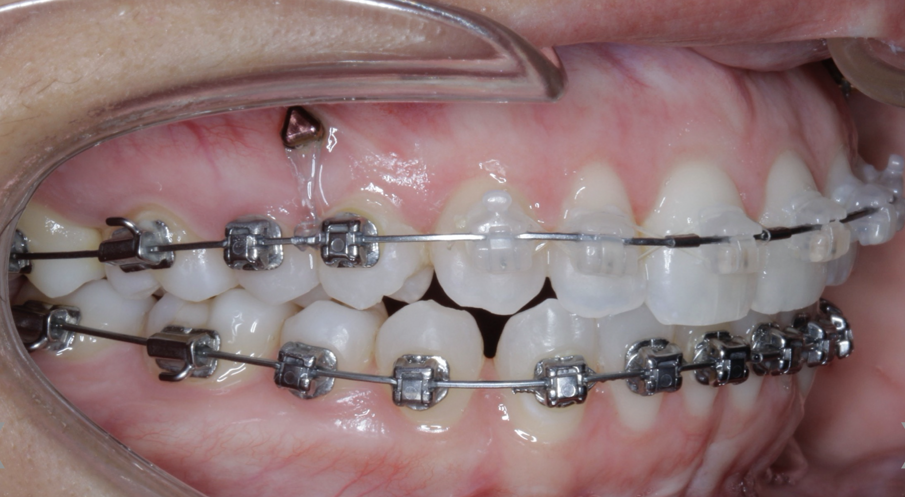

TADs are placed at the second visit with a 14 × 25 mm copper (Cu) and nickel–titanium (NiTi) wire and are tied from the anchor to the wire with an elastic thread (surgical thread; Fig. 6). Once the patient has progressed to larger Cu–NiTi wires and stainless steel, the TADs are tied to the wire using a power chain looped to the wire, or NiTi closing springs, depending on the thickness of the tissue (Figs. 7 & 8).